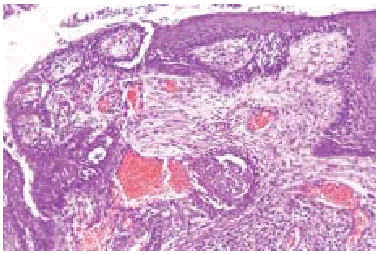

Fig. 3.--El estudio histopatológico de las lesiones tumorales en ambos casos mostraba áreas de carcinoma epidermoide bien diferenciado.

Un varón de 75 años de edad sin antecedentes patológicos de interés, presentaba desde la juventud en la región pectoral derecha una lesión que había crecido progresivamente y por la que nunca había consultado. En la exploración se apreciaba una placa de 10 x 6 cm infiltrada al tacto, de piel atrófica y de color amarillento, que alternaba áreas hipo e hiperpigmentadas. Sobre ella, desde hacía 3 años se habían desarrollado elementos ulcerovegetantes de crecimiento rápido. Se realizó una biopsia cutánea cuyo estudio histopatológico mostró la presencia granulomas tuberculoides sin apenas necrosis, con áreas de carcinoma epidermoide bien diferenciado. La tinción de Ziehl-Neelsen fue negativa. En el cultivo de un fragmento de la biopsia cutánea se aislaron escasas colonias de M. tuberculosis. Entre los estudios complementarios realizados destacaba una prueba de la tuberculina positiva con induración de 15 mm, una radiografía de tórax sin focos alveolares ni secuelas de tuberculosis y un hemograma y bioquímica de sangre y orina sin alteraciones. No se pudo comprobar la presencia de infección tuberculosa en otro órgano. Se realizó la exéresis quirúrgica de la lesión con reconstrucción del defecto mediante un injerto mallado de piel parcial. El paciente recibió tratamiento tuberculostático durante 6 meses. A los 2 años del tratamiento no se ha observado recidiva del carcinoma epidermoide ni nuevas lesiones de lupus vulgar.

Un varón de 97 años de edad presentaba desde los 33 años unas lesiones localizadas en la frente y en las mejillas que habían progresado lentamente formando una placa atrófica y cicatrizal de tinte ligeramente anaranjado. La lesión afectaba también a los pabellones auriculares y los destruía parcialmente. Tres años antes de la consulta había desarrollado una tumoración en el centro de la frente que fue tratada entonces mediante legrado y electrocoagulación en otro centro, sin realizar estudio anatomopatológico. En los últimos 2 años había desarrollado una neoformación en el pabellón auricular izquierdo y desde hacía 6 meses había reaparecido la tumoración frontal de crecimiento rápido. La tomografía computarizada (TC) demostró que la tumoración frontal, de 10 cm de diámetro, destruía las paredes de la órbita izquierda y afectaba el globo ocular. El estudio histológico de la lesión frontal y del pabellón auricular demostró la presencia de un carcinoma epidermoide, mientras que el estudio anatomopatológico del resto de la lesión facial mostraba numerosos granulomas tuberculoides sin apenas necrosis caseosa (fig. 3). El cultivo para micobacterias de la biopsia cutánea fue negativo y tampoco se hallaron bacilos ácido-alcohol resistentes mediante la tinción de Ziehl-Neelsen. La prueba de la tuberculina fue positiva, con eritema e induración de 18 mm. No se encontró infección tuberculosa en otros órganos o sistemas. Dada la avanzada edad del paciente y el tamaño de los carcinomas epidermoides, se realizó radioterapia local que consiguió una reducción significativa de la masa tumoral. Además recibió tratamiento tuberculostático durante 6 meses con mejoría de las lesiones de lupus vulgar. El paciente falleció al año y medio del diagnóstico a consecuencia de una neumonía bacteriana extrahospitalaria.